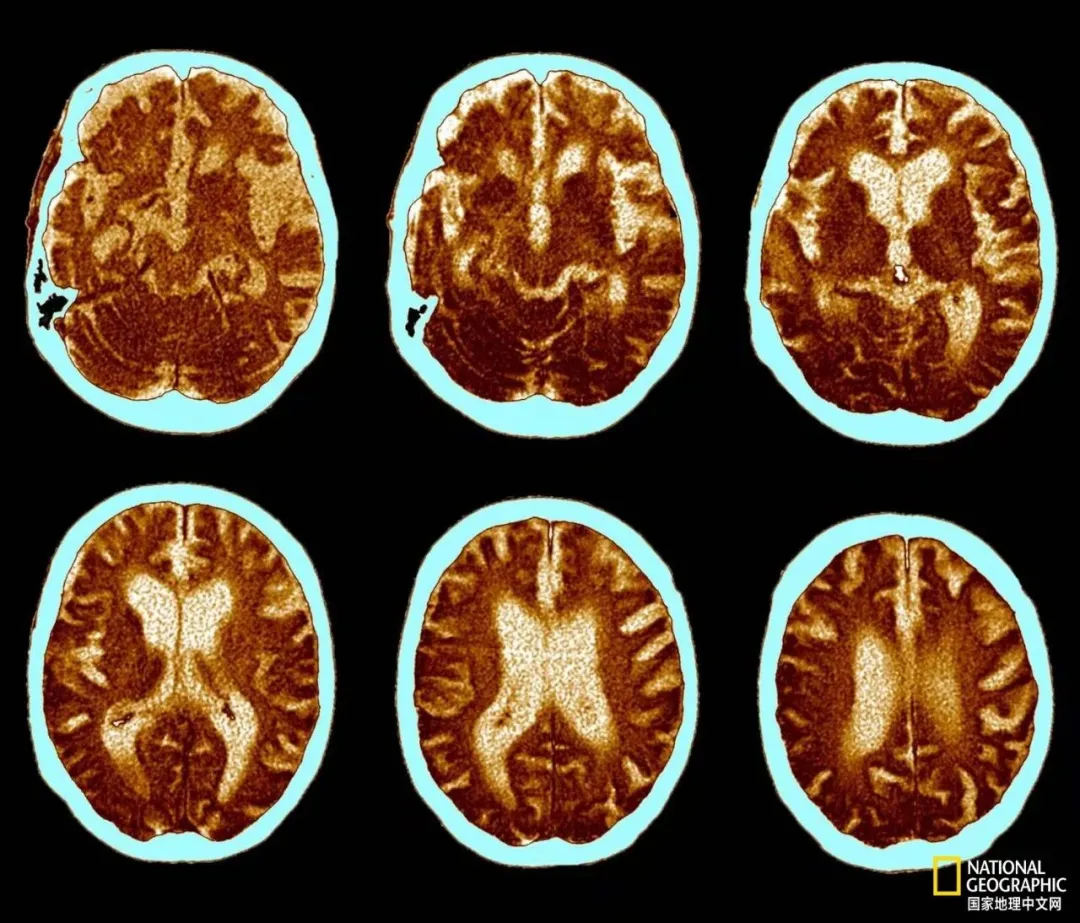

这是一位74岁阿尔茨海默病患者的脑部扫描图,清晰地揭示了该病如何导致大脑萎缩。图中可见脑室腔扩大,以及淡蓝色区域增宽,这些都是脑萎缩的典型表现。这种大脑萎缩会引发记忆力减退、意识模糊以及性格改变等症状。|国家地理图片集